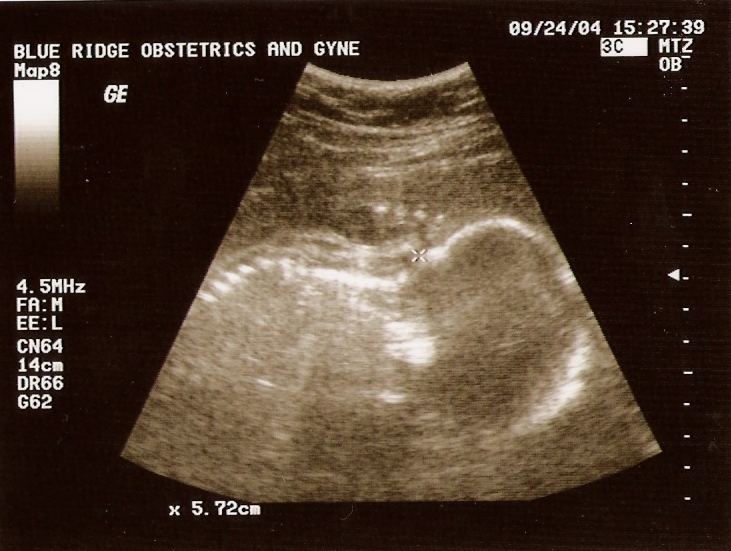

Ultrasound

Taken On June 2nd 2004   Taken On September 24th 2004   Taken On October26th 2004